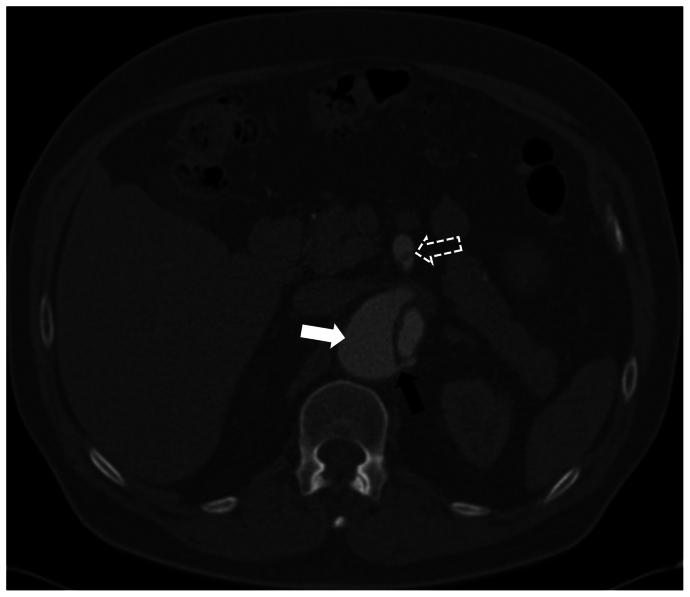

Fenestration of the septum between the true and false lumen might be necessary after aortic dissection. We report the technical aspects of in situ laser fenestration of the aortic dissection septum. Two illustrative cases are provided: a 56-year-old man with false lumen deployment of a frozen elephant trunk graft, and a 67-year-old man who underwent fenestrated endovascular aortic repair with a target branch vessel off the false lumen. In both cases, the septum was crossed using in situ laser fenestration. This technique is a precise option to enable passage between true and false lumens during endovascular repair of an aortic dissection.